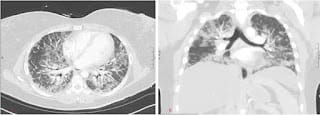

Ghosh recuerda que McGonagle le habló de pacientes con lesiones pulmonares graves, algunos de los cuales presentaban síntomas reumatológicos (erupciones cutáneas, artritis, dolor muscular) que, a menudo, acompañan la enfermedad pulmonar intersticial. McGonagle tenía curiosidad por saber si existía una conexión entre la dermatomiositis positiva para MDA5 y el covid-19.

Un total de 25 pacientes desarrollaron cicatrices pulmonares (enfermedad pulmonar intersticial) y 8 personas del grupo mostraron un cuadro lo suficientemente grave como para provocar la muerte debido a la fibrosis progresiva. Ghosh señaló que existían perfiles clínicos establecidos de enfermedades autoinmunes MDA5. “Pero esto fue diferente”, advirtió. “Fue diferente en el comportamiento y la tasa de progresión, y en el número de muertes”, expuso.